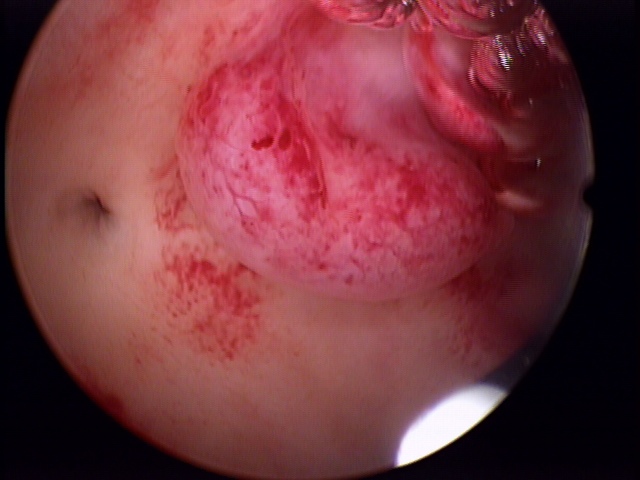

Os pólipos são caracterizados pelo crescimento anormal e em um único ponto do tecido que reveste a parte interna do útero. Habitualmente, a suspeita é detectada na ultrassonografia transvaginal de rotina e o diagnóstico concluído pela histeroscopia diagnóstica ambulatorial.

Os pólipos intrauterinos podem causar cólicas irregulares, hemorragias e corrimentos, afetando a fertilidade feminina na fase reprodutiva da mulher.

A retirada dos pólipos endometriais é indicada quando nota-se crescimento do mesmo e, consequentemente, sintomas desse crescimento ou quando há necessidade de estudo anatomopatológico para verificação de malignidade ou em casos de infertilidade.